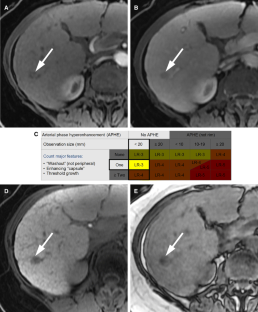

LI-RADS® algorithm: CT and MRI

The Liver Imaging Reporting and Data System (LI-RADS®) is an imaging-based diagnostic system applicable in patients at high risk of hepatocellular carcinoma (HCC). In LI-RADS, each liver observation is assigned a category that reflects probability of benignity, HCC, or other malignancy. Familiarity with the LI-RADS diagnostic algorithm is necessary to appropriately implement LI-RADS in clinical practice. This review discusses steps necessary for application of the LI-RADS algorithm and provides examples illustrating each step.